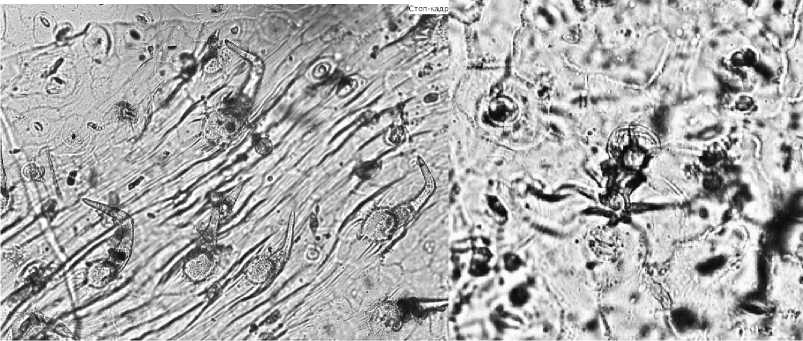

Воздушно-сухое сырье представляет собой цельные травянистые побеги, заготовленные во время цветения. Стебли ветвистые, четырехгранные, темнозеленого цвета. Листья ланцетные или линейно-ланцетные, в длину от 2 до 4 см, темно-зеленые, нижняя сторона покрыта опушением. Соцветие — кисть. Цветки двугубые, сине-фиолетовые, длина чашечки и венчика 4–7 мм. Аромат сырья насыщенный, характерный. Вкус водного извлечения пряно-горьковатый. При изучении микропрепарата листа с его поверхности видно, что клетки верхнего эпидермиса имеют слегка изогнутые стенки (рис. 1)

Рис. 1. Лист — верхний эпидермис диацитного типа с эфирномасличной железкой Клетки нижнего эпидермиса сильноизвилистые (рис. 2).

Рис. 2. Лист — нижний эпидермис диацитного типа с извилистыми стенками

Устьица овальной формы диацитного типа. На обеих поверхностях листа встречаются простые одно- и трехклеточные волоски с бородавчатой поверхностью (рис. 3а). Между ними головчатые волоски с одноклеточной ножкой и шаровидной одно- и двухклеточной головкой (рис. 3б).

а

б

Рис. 3. Лист — верхний эпидермис (а — многочисленные простые волоски с бородавчатой поверхностью; б — головчатый волосок)

На поверхности чашелистиков наблюдаются многочисленные простые двухклеточные волоски с бородавчатой поверхностью, между ними встречаются головчатые волоски с двухклеточной ножкой (рис. 4а).

По всей поверхности лепестков в большом количестве идентифицируются многочисленные крупные округлые эфирномасличные железки с коричневым содержимым. Эфирномасличные железки округлые, расположены по радиусу и состоят из восьми выделительных клеток. Также на поверхности лепестков в большом количестве присутствуют одно-, двухклетчатые бородавчатые волоски и редко встречаемые голововчатые (рис. 4б).

Рис. 4. Венчик (а — извилистые клетки; б — эфирномасличные железки и головча- тые волоски с двухклеточной ножкой)